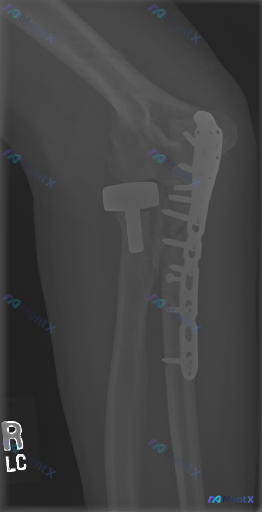

- 右肘做过两个手术:尺骨近端背侧锁定钢板(跨鹰嘴)+ 桡骨头金属假体置换

- 报告写“内固定物及假体在位,未见明确松动、断裂或再骨折”

- 但也提了一句“常规脂肪垫征不易评估”